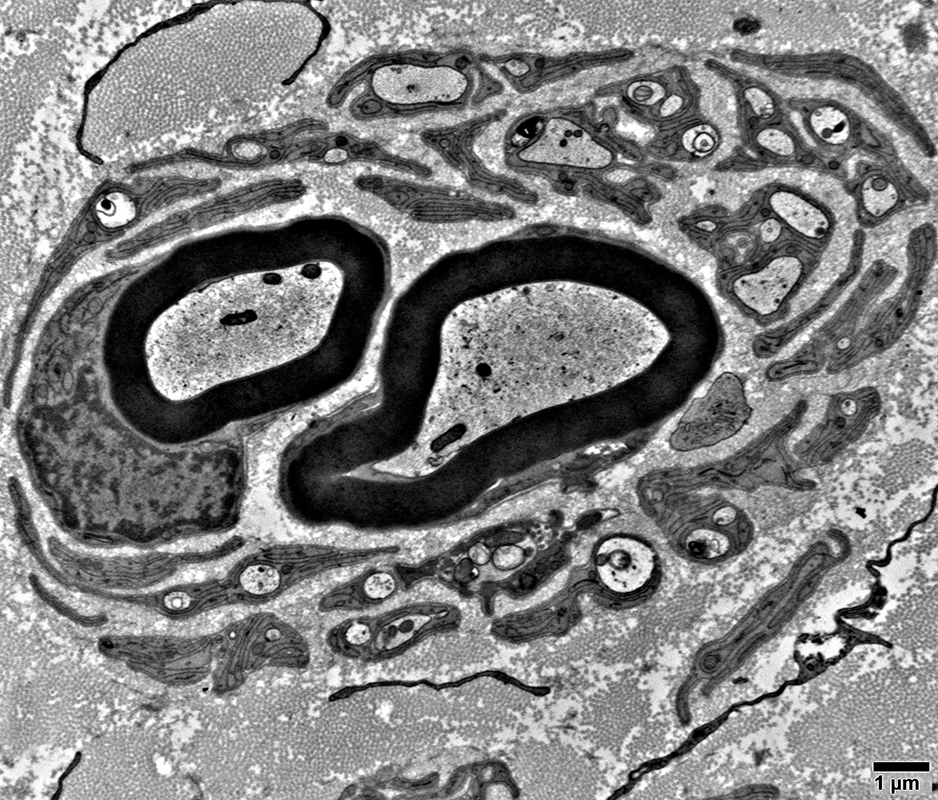

Pseudo-Onion bulbs

Multiple Schwann cell processes surround regenerated, thinly myelinated, axons

Pseudo-Onion bulbs, Complex

Schwann cell processes surround central axon

Myelinated axons surrounded by non-myelinating Schwann cells

Some non-myelinating Schwann cells surround small unmyelinated axons